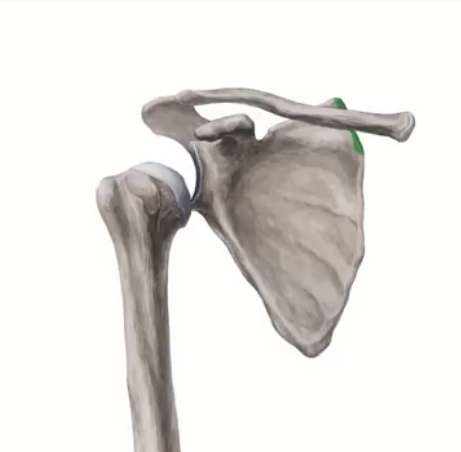

Patologie della Spalla

Lesione della cuffia dei rotatori

Il dolore alla spalla irradiato al braccio che aumenta con lo sforzo e di notte è spesso il primo sintomo di una patologia della Cuffia dei Rotatori.

Tendinopatia calcifica

La tendinopatia calcifica è una patologia dolorosa della spalla caratterizzata dalla presenza di depositi di sali di calcio all’interno dei tendini della cuffia…

Artrosi gleno-omerale

Nell’artrosi il tessuto cartilagineo viene progressivamente ed irreversibilmente danneggiato. Le superfici ossee…